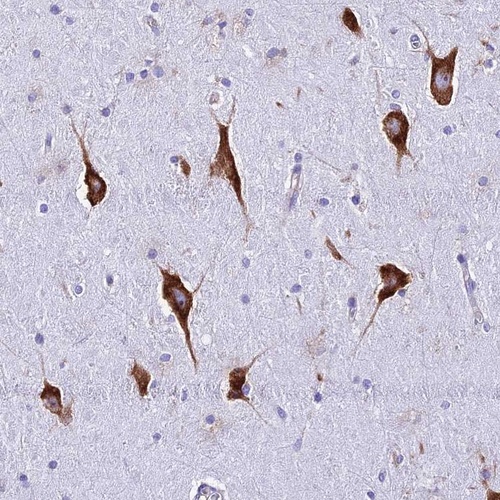

Immunohistochemical staining of human hippocampus shows strong cytoplasmic positivity in neuronal cells.